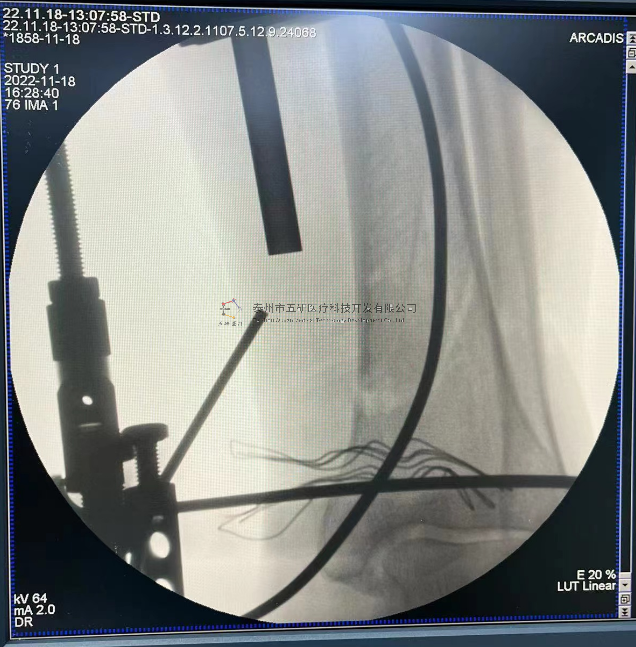

本病例由中國中醫(yī)科學院望京醫(yī)院骨關二提供(術者:支架主任蔣主任)

【基本資料】患者,男,41歲

本病例踝關節(jié)骨折。手術名稱:左踝關節(jié)骨折外固定支架手術

【手術資料】